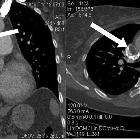

Giant mass

but small symptoms; huge thrombosis in the right atrium originating from the superior vena cava and protruding to the right ventricle: a case report. Computed tomographic angiography demonstrating a filling defect in the superior vena cava. The arrow is pointing to these filing defects